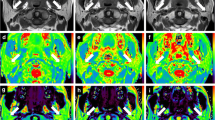

As shown in Table 3 and Fig. 3, the change rates of parotid ADC, f and MRE were negatively correlated with the atrophy rate significantly from pre-RT to post-RT (all p < 0.05). There was no significant correlation between mean radiation dose and any change rate of parotid IVIM or any DCE MR parameter (all p > 0.05).

Scatter plots show that the change rates of apparent diffusion coefficient (ADC) (a), perfusion fraction (f) (b) and maximum relative enhancement (MRE) (c) values are significantly correlated with the parotid atrophy rate from pre-RT (approximately 2 weeks before radiotherapy) to post-RT (approximately 4 weeks after radiotherapy). RADC, Rf and RMRE are the change rates of ADC, f and MRE values from pre-RT to post-RT, respectively. The dashed lines are the 95 % confidence bands